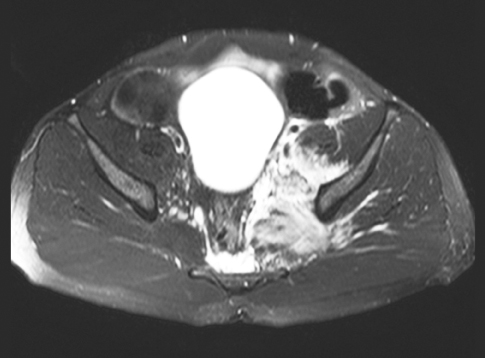

Seema Kapur, MD; Gregory W. Rutecki, MD

<p>2 cases of adults with MRSA infections complicated by left transverse, sagittal cerebral venous thromboses with septic emboli to the lungs and bilateral iliac vein thrombosis,...

02/08/2012